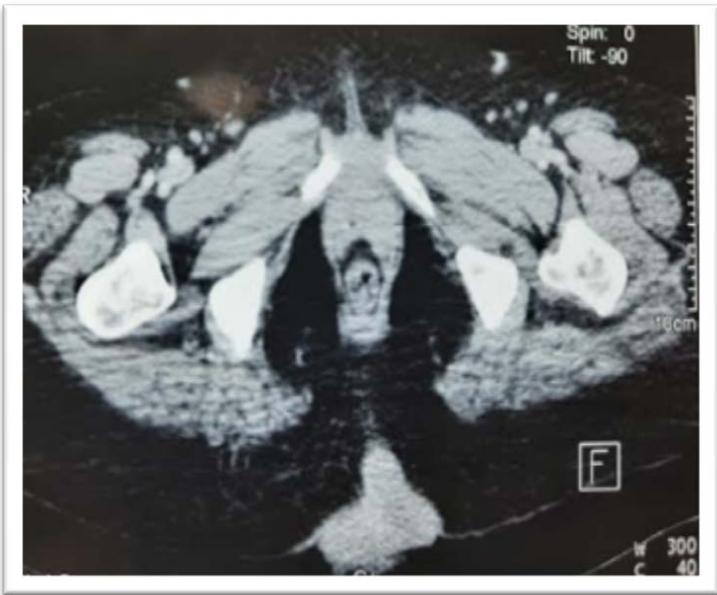

We report the case of a 63-year-old woman, without any notable pathological history, who presented for one year with a bulging right gluteal mass that was progressively increasing in size. This mass was palpable to the firm touch, sensitive to the contact and was bleeding. It was located in the right lower gluteal quadrant and fixed relative to the gluteal muscle (Figure 1). Helical imaging was performed after intravenous contrast injection, revealing a large hypodense tissue mass occupying the right gluteal region, measuring $12 \times 8.1 \, \text{cm}$ with no other secondary locations (Figure 2).

Figure 2: Computed tomography scan showing gross mass of the region Gluteal